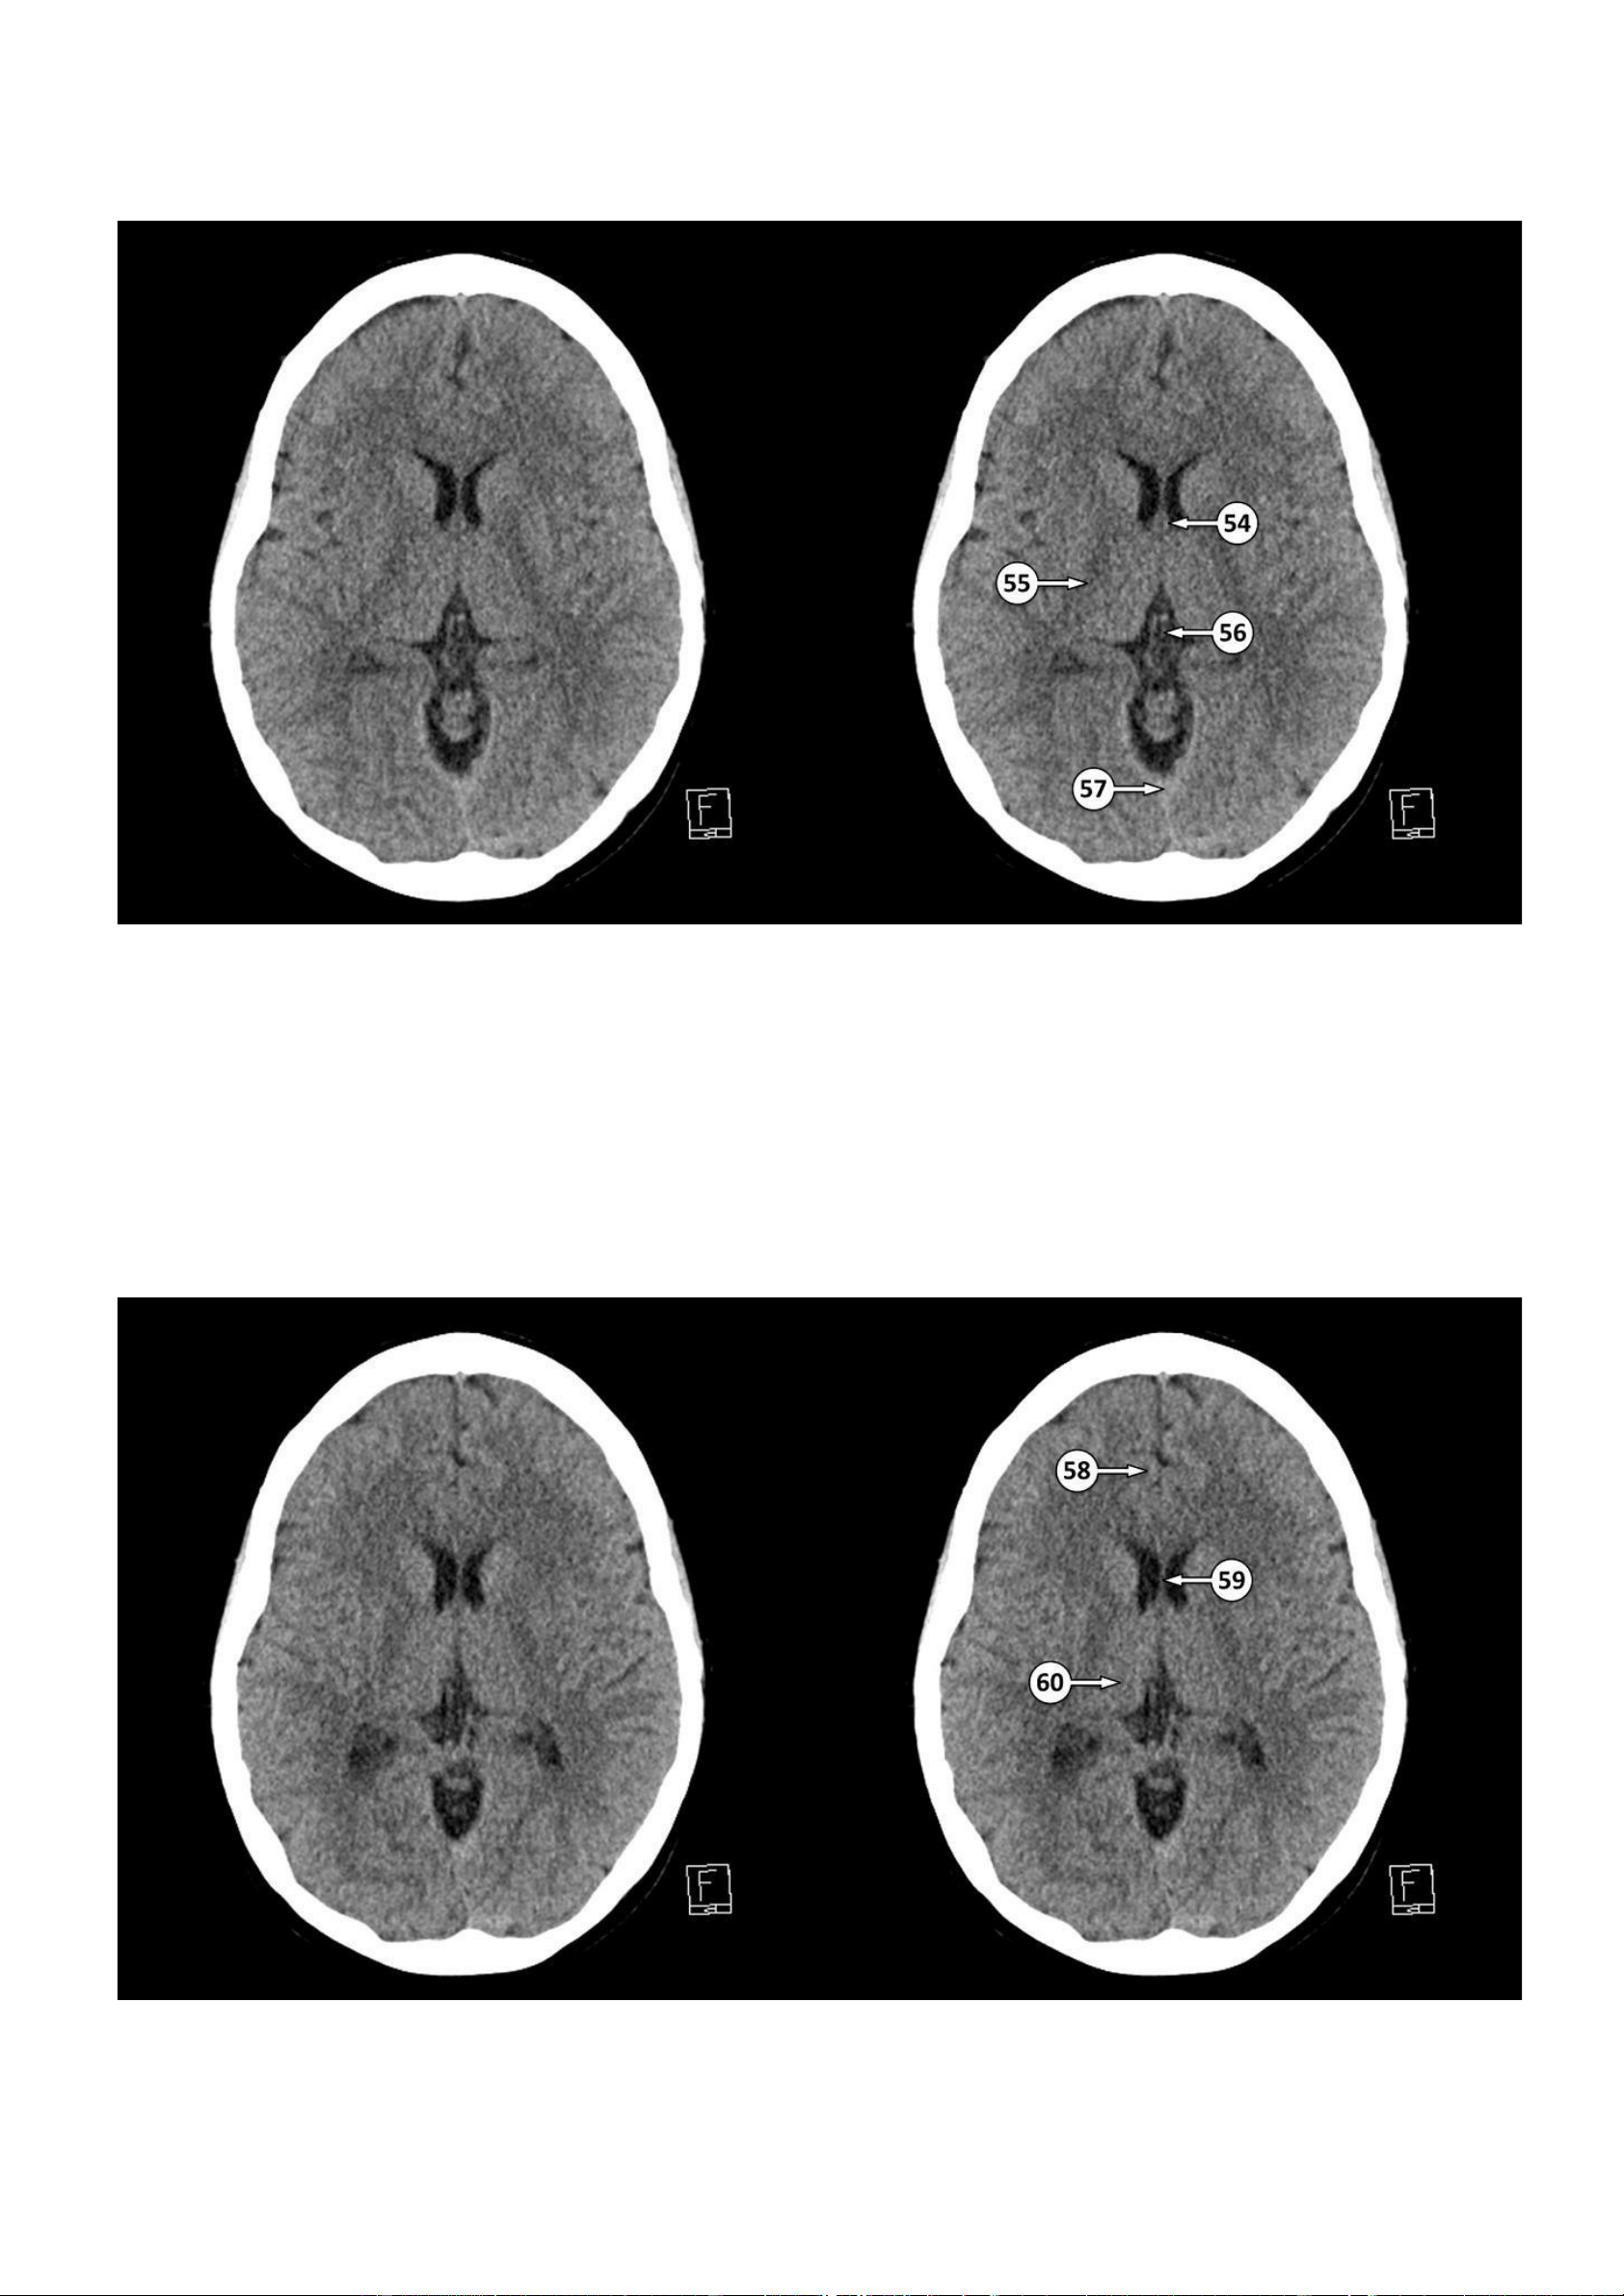

▪ Số 54: Cột của vòm não

▪ Số 55: Cánh tay sau của bao trong

▪ Số 56: Tĩnh mạch não trong ▪ Số 57: Xoang thẳng 58: Hồi đai lOMoAR cPSD| 22014077

Thảo Thảo & Bé Nghìn Dặm 59: Vách trong suốt 60: Đồi thị ▪ Số 61: Bó nhỏ

▪ Số 62: Hợp lưu sừng chẩm và sừng thái dương của não thất bên ▪ Số 63: Thuỳ chẩm lOMoAR cPSD| 22014077

Thảo Thảo & Bé Nghìn Dặm 64: Lồi của thể chai